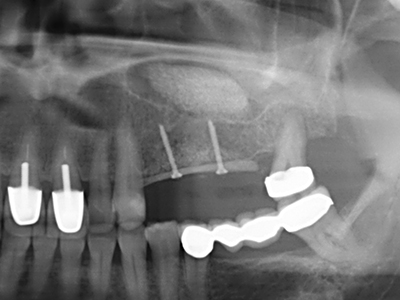

Fig. 15: The one-year follow-up x-ray examination shows stable conditions at the bone level.

Bone tissue is not simply a mineral structure but also contains a substantial proportion of collagen fibres. This means it not only has good compressive strength but also a degree of flexibility, which can be taken advantage of when performing bone augmentations. In the classical expansion procedure using bone splitting, the atrophied alveolar ridge is split longitudinally and carefully expanded after reaching an adequate osteotomy depth (Fig. 13-16), ideally without substantial removal of the periosteum (Brugnami, Caiazzo et al. 2014, Stricker, Fleiner et al. 2014). Screw and plate systems with increasing expansion distance have proven effective in separating the two bone lamellae while remaining below the fracture threshold. In general, residual bone widths of at least 3–4 mm are required (Chiapasco, Zaniboni et al. 2006) to guarantee adequate flexibility and sufficient bone coverage of the future implants. If necessary, a vertical relief osteotomy on one or both sides can improve flexibility. A combination with additional augmentation techniques, particularly on the buccal side, has been described as an alternative to the classical technique.

The splitting procedure is particularly atraumatic and there is no significant loss of dimension when using piezosaws, and there are no significant differences between implants in split jaws and implants in an alveolar ridge without a bone deficit (Chiapasco, Zaniboni et al. 2006, Danza, Guidi et al. 2009). However, sufficient continuous irrigation is essential, particularly with locally restricted and deep splitting to prevent thermal stress in the apical osteotomy regions.

Fig. 13: Adequate irrigation with the 4-mm residual bone width is essential for this 52-year-old patient during the bone splitting.

Fig. 14: Placement of four tapered RSX implants (Bego Implant Systems, Bremen).